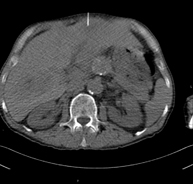

- Abdominal and pelvic CT

Diagnostic test that consists of obtaining high-definition anatomical images (bone structures, vascular structures, liver, pancreas, gallbladder, kidneys, adrenal glands, spleen, small and large intestine, bladder, uterus and ovaries, prostate and seminal vesicles, ureters, etc.) using CT (computed tomography) equipment. Most studies require the use of iodinated contrast.